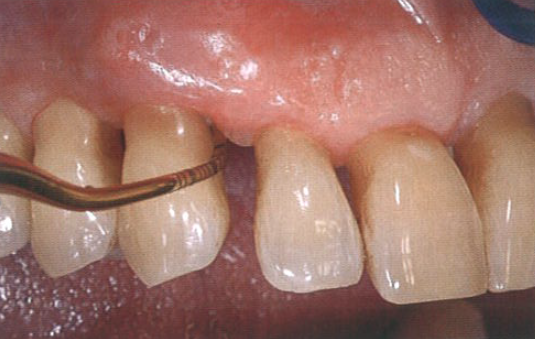

在之后的每次随访复诊中,该区域都被密切监测,并且在使用半导体激光治疗后1年,临床状态似乎已经稳定。图3为急性发作5年后的牙周情况,总随访时间为20年。这张图片说明患者的牙周状况保持稳定,探诊深度约为3 mm,无探诊出血。

图3  急性发作5年后,患者探诊深度约为3 mm,无探诊出血,牙周状况保持稳定